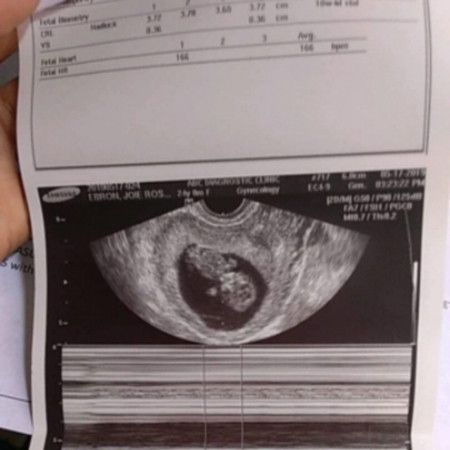

Hello. Malalaman po ba sa ultrasound if mababa ung matres mo or hindi? 10 weeks 4 days ko napo nalaman na buntis po pala ako since irregular po ako and once a month lang kame magsex and always withdrawal po ginagawa namin. And nung nagpacheck up po kame snbihan po ako ng doctor na baka daw PCOS to. Pero nung nagpaultrasound po ako yan po ung result. Thank you sa mga sasagot :) Madami lang akong gustong malaman since 1st baby ko po sya ?

nung pregnant ako sa bunso ko, sobrang worried ako kasi been through an emergency CS and D&C na ang pagitan ay 6mos lang then nagpositive ako na pregnant 2mos after nung raspa. ang concern ko baka mababa matres ko so i asked sa OB. sabi sakin, walang ganun. san ba dapat ang matres? dyan naman talaga yan hindi naman nasa dibdib. baka po placenta? makikita po sa ultrasound yung pwesto ng placenta kung high or low lying. pero pwede pa din po tumaas yung low lying kapag nag expand na yung uterus. machcheck po yun sa ultrasound din after a few months.